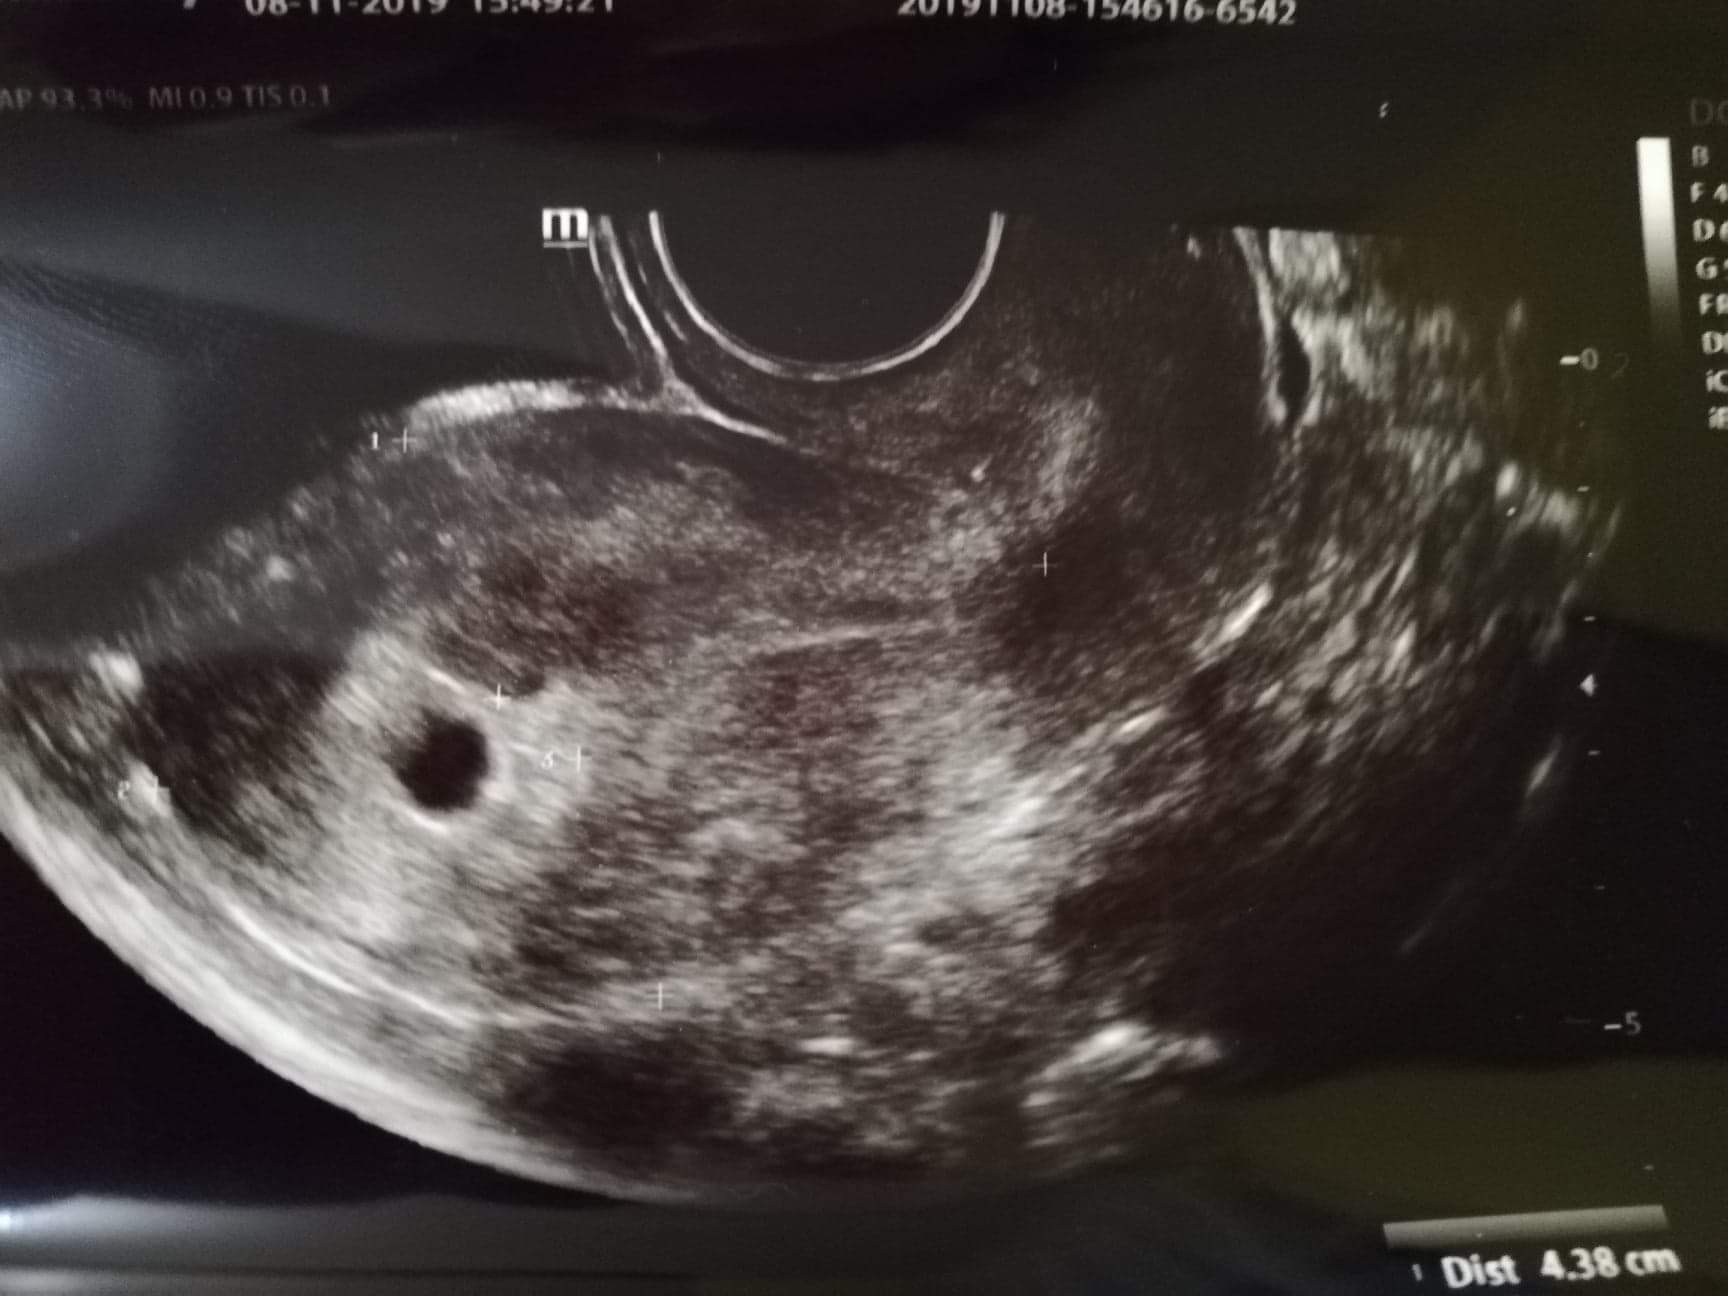

Witamitawegaminka USG[emoji173][emoji173][emoji173]

@Witamitawegaminka USG[emoji173][emoji173][emoji173]